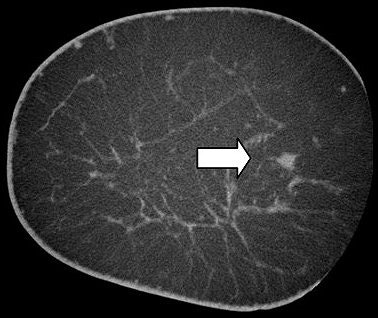

According to the results, the mean scanning time was 12 seconds for images that were deemed adequate for tissue visualization and 48 seconds for high-resolution images. On the latter, cancer appeared as an "irregular spiculated mass with associated microcalcifications or overlying skin thickening, or an area of focal asymmetry."

Microcalcifications within cancers were clearly seen with conebeam CT imaging (American Journal of Roentgenology, December 2007, Vol. 189:6, pp. 1312-1315).

![]() |

| A 63-year-old woman with invasive ductal carcinoma of left breast. Coronal CT image shows microcalcifications within area of architectural distortion representing known cancer (arrows). Pathology showed ductal carcinoma in situ associated with microcalcifications. Yang WT, Carkaci S, Chen L, Lai C, Sahin A, Whitman GJ, and Shaw CC, "Dedicated Cone-Beam Breast CT: Feasibility Study with Surgical Mastectomy Specimens" (AJR 2007; 189:1312-1315). |